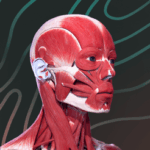

Essential Anatomy 5 IPA Are you a medical student or a professional in the healthcare field looking for a reliable and comprehensive anatomy app? Look no further because Essential Anatomy 5 IPA is here to fulfill all your anatomical needs. In this article, we will explore the benefits and features of this amazing app, and guide you through the process of downloading it for free on your iOS device. So, let’s dive into the world of Essential Anatomy 5 IPA and discover how it can revolutionize your understanding of the human body.

Downloading Essential Anatomy 5 IPA for iOS is a convenient and useful way to explore the world of human anatomy right from the comfort of your iPhone or iPad. This app provides a comprehensive and detailed view of the human body, allowing users to interact with various systems and structures. With stunning 3D graphics, it offers a visually captivating experience that aids in understanding and learning about the complexities of the human body. Whether you are a medical student, healthcare professional, or someone with a general interest in anatomy, Essential Anatomy 5 IPA is a must-have app that provides a wealth of knowledge at your fingertips. The app’s intuitive interface and easy navigation make it accessible to users of all levels of expertise. With just a few taps, you can delve into different layers of the body, explore various organs, muscles, and bones, and gain a deeper understanding of human anatomy. Download Essential Anatomy 5 IPA today and elevate your knowledge and appreciation of the human body.

The Essential Anatomy 5 IPA for iPhone is an incredible tool for medical students, professionals, and anyone interested in learning more about the human body. This app provides a comprehensive and detailed 3D model of the human anatomy, allowing users to explore and study different parts of the body with ease. With its user-friendly interface and interactive features, users can zoom in, rotate, and examine every angle of the human body, from bones and muscles to organs and systems. The app also provides in-depth information about each structure, making it a valuable resource for studying and understanding the intricacies of human anatomy. Whether you’re a medical student preparing for exams or simply curious about the wonders of the human body, the Essential Anatomy 5 IPA for iPhone is an essential tool to have at your fingertips.

Essential Anatomy 5 IPA MOD IOS is a revolutionary app that has changed the way we learn about the human body. With its advanced features and stunning visuals, this app provides an immersive and interactive experience for users. Whether you are a medical student, healthcare professional, or simply interested in learning about anatomy, Essential Anatomy 5 is a must-have tool. It offers a comprehensive library of detailed 3D models, allowing users to explore every aspect of the human body. From the skeletal system to the muscular system, nervous system to cardiovascular system, this app covers it all. Additionally, it provides in-depth information on each structure, including names, functions, and clinical relevance. With its user-friendly interface and intuitive controls, navigating through the app is a breeze. Overall, Essential Anatomy 5 IPA MOD IOS is an essential resource that brings anatomy to life, making it an invaluable tool for anyone interested in the human body.

This app provides a comprehensive and detailed 3D representation of the human body. With over 8,200 anatomical structures, including muscles, bones, organs, and more, it offers a level of accuracy and depth that is unparalleled. Whether you are studying for an exam or explaining a medical condition to a patient, Essential Anatomy 5 IPA has the information you need.

Essential Anatomy 5 IPA is an indispensable tool for anyone involved in the study or practice of medicine. With its comprehensive and detailed 3D models, interactive features, cross-sectional views, and personalized learning options, this app is revolutionizing the way we understand and engage with the human body. So, if you’re ready to take your anatomical knowledge to the next level, download Essential Anatomy 5 IPA for free on your iOS device today and embark on a fascinating journey through the intricacies of human anatomy.